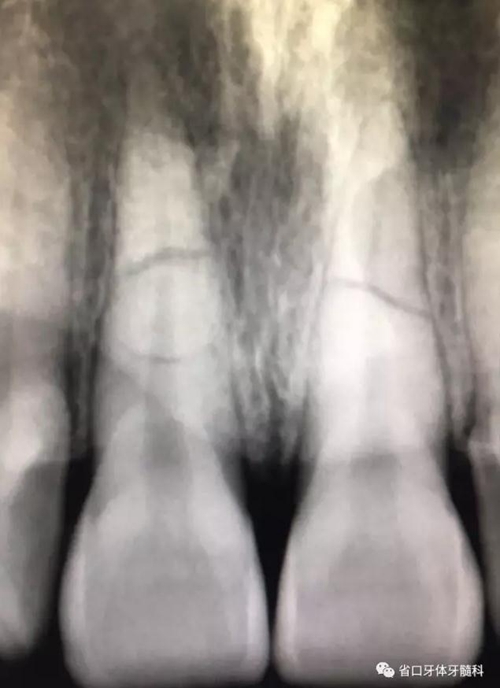

圖2 術(shù)前根尖片

X線片:11、21根中段見(jiàn)橫行根折線,無(wú)移位,根尖無(wú)明顯異常。